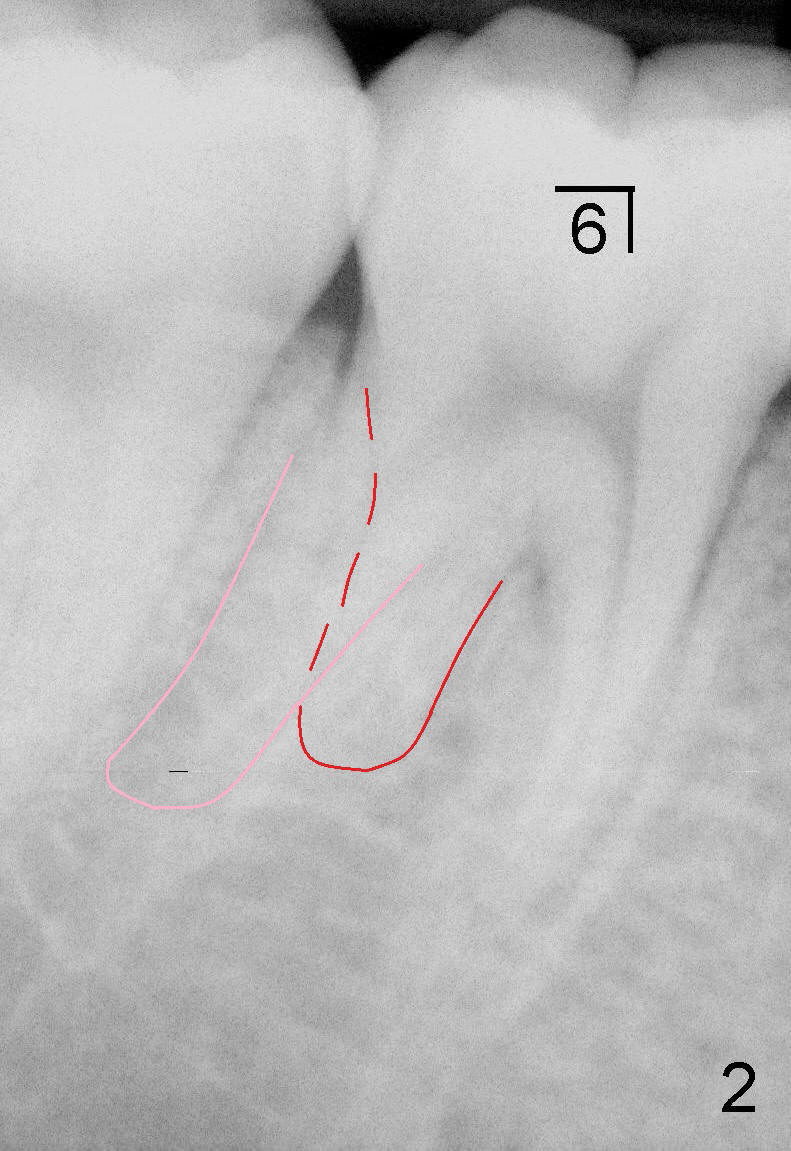

首先分析下颌第一磨牙(图二):远中有两个根(颊侧:粉红色轮廓;舌侧(红色)。东方人第一磨牙远中两个牙根比较常见。